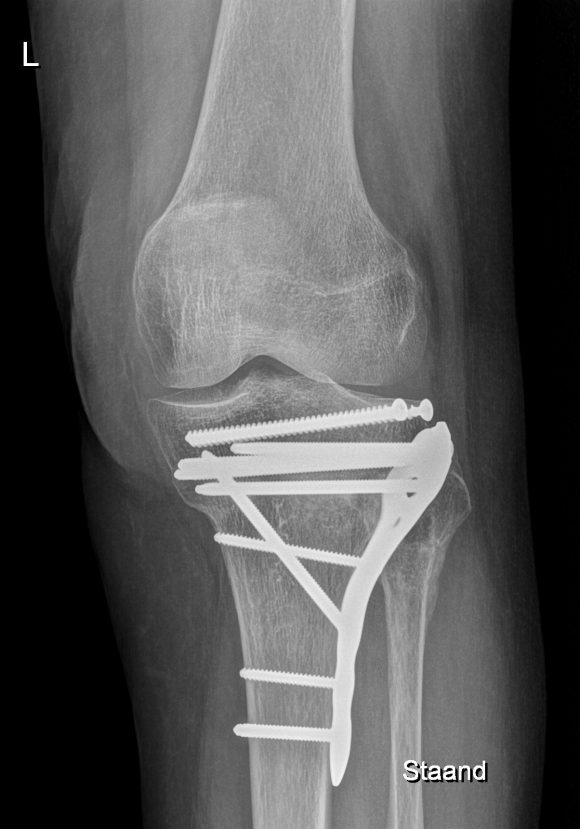

Kniefractuur

Breuk in of rond de knie na val of sportongeval? Kniefractuur diagnose en operatieve behandeling door kniespecialisten in Orthopedie Turnhout.